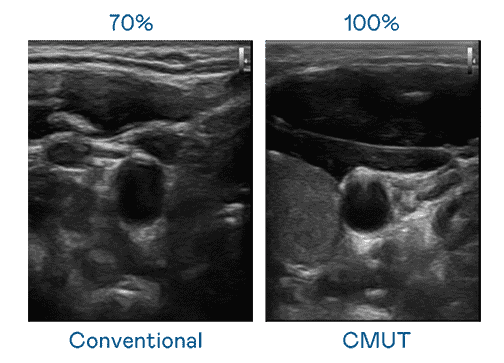

CMUT 技术是一种用电容式微机电元件来产生超音波讯号的技术。。与传统 PZT 压电式技术相比,,CMUT 频宽增加 30%,,,,更宽频的超音波讯号让影像解析度大幅提升,,,是实现高影像品质医疗超音波扫描、、促进精准医疗发展的关键技术。。

大频宽带来超清晰影像

超音波影像的解析度高低,,,,首先取决于探头能发出的讯号频宽。。918.COM CMUT 可提供高清晰的超音波讯号,,,,提供高频宽、、、高灵敏度、、影像纹理细节更高的超音波影像,,,协助医护人员缩短影像判读时间及利用精准的医疗影像进行诊断。。